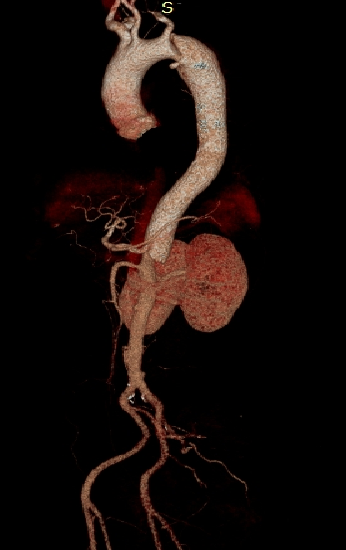

男性,44岁,慢性B型夹层。2010年12月行TEVAR术。

2013年5月发现RTAD,未处理。2015年2月死亡。

▎病例二

男,52岁,慢性夹层。2015年8月入院,4年前曾因B型层行TEVAR术,主动脉解剖变异,扭曲。行双烟囱+TEVAR术。术后第3天RTAD ,死亡。

▎病例三

男,60岁,慢性夹层。2013年12月行Debranching+TEVAR术 。2016年7月复查: RTAD ,未手术。失访。